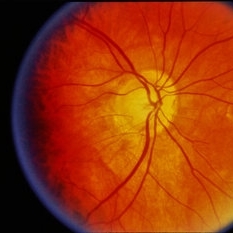

---thumb.jpg/image-square;max$300,300.ImageHandler) Age Related Macular Degeneration

Age Related Macular Degeneration

May 3 2013 by Suber S. Huang, MD, MBA, FASRS

Age related macular degeneration.

Condition/keywords: advanced geographic atrophy, atrophic scar, atrophic spot, geographic atrophy, macula lesion, pigment epithelial atrophy, red-free, window defect